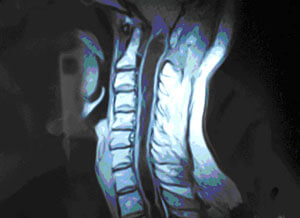

SIRINGOMIÝELIÝA

Siringomiýeliýa (grek dilinde sirinx - gamyş, boş tüýdük; miýelon - oňurga ýiligi) – dowamly kesel bolup, oňurga ýiliginde we süýri beýnide boşluklaryň emele gelmegi bilen häsiýetlendirilýär. Bu üýtgemeleriň netijesinde bedeniň uly meýdanlarynda  agyryny we temperaturany aňşyrmak duýgurlylygy ýitýändir.

Emele gelýän boşluklar adatça oňurga ýiliginiň boýun bölüminiň aşaky böleginde, döş bölüminiň ýokarky böleginde ýa-da boýun bölüminiň ýokarky böleginde emele gelip, süýri beýnä (siringobulbiýa) ýaýrap biler. Seýrek ýagdaýlarda bil bölümi ýa-da tutuş oňurga ýiligi zeperlenip bilýändir.